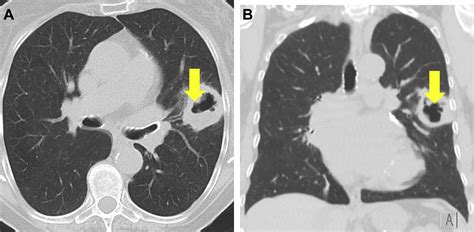

Distinguishing Features on Imaging

Radiologists look for specific markers to help narrow down the diagnosis. The appearance of the cavity's wall, for instance, provides vital clues:

• Thick, Irregular Walls: These are more suggestive of malignancy (e.g., squamous cell carcinoma).

• Thin, Smooth Walls: Often point toward benign causes, such as a congenital cyst or a resolved infection (pneumatocele).

• Air-Fluid Levels: Highly indicative of a lung abscess, suggesting a collection of pus that has not yet been fully drained.